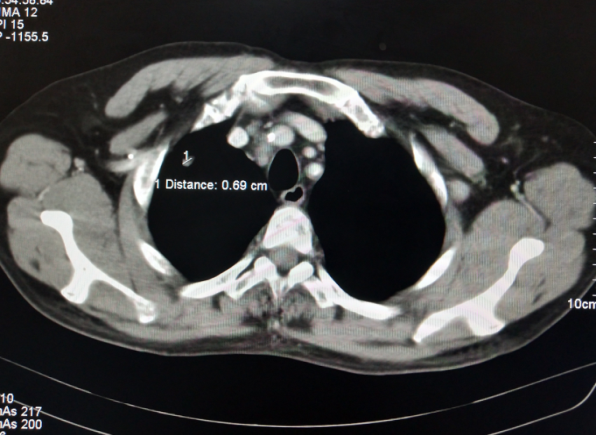

术前病灶测量

术中精准穿刺